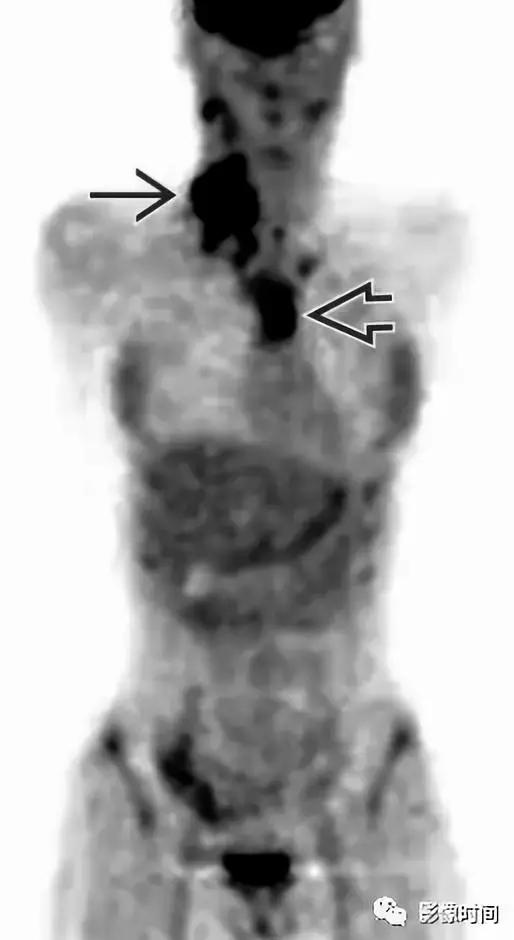

FDG-PET 冠状图像显示右侧颈部和纵隔霍奇金淋巴瘤有明显的活动。